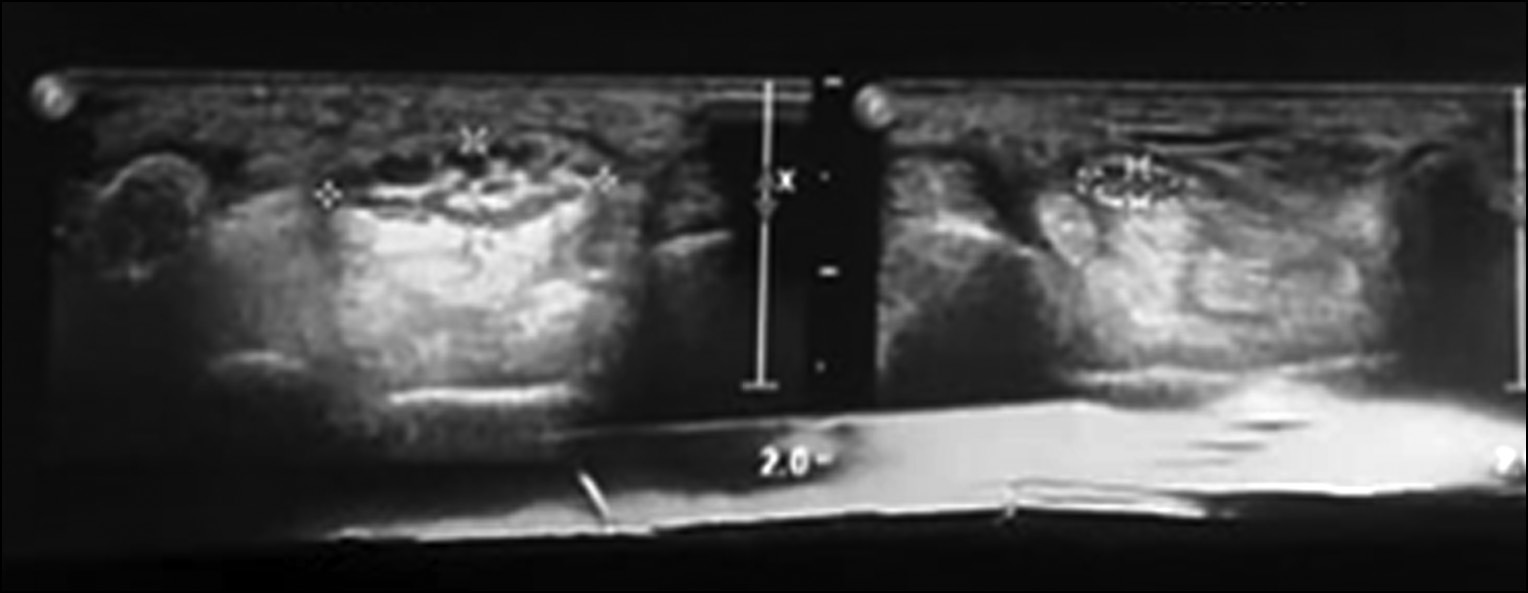

УЗИ позволило точно определить локализацию опухоли, её границы и размеры, эхогенность, характер взаимоотношения с окружающими тканями, а также исследовать близлежащие структуры и их вторичные изменения (рис. 8). Сочетание УЗИ с цветным допплеровским картированием дало возможность определить степень васкуляризации патологического очага.

Рис. 8. Ультрасонограмма опухолевидного образования (нейрофиброматоз) срединного нерва.

Fig. 8. Ultrasonogram of a tumor-like formation (neurofibromatosis) of the median nerve.